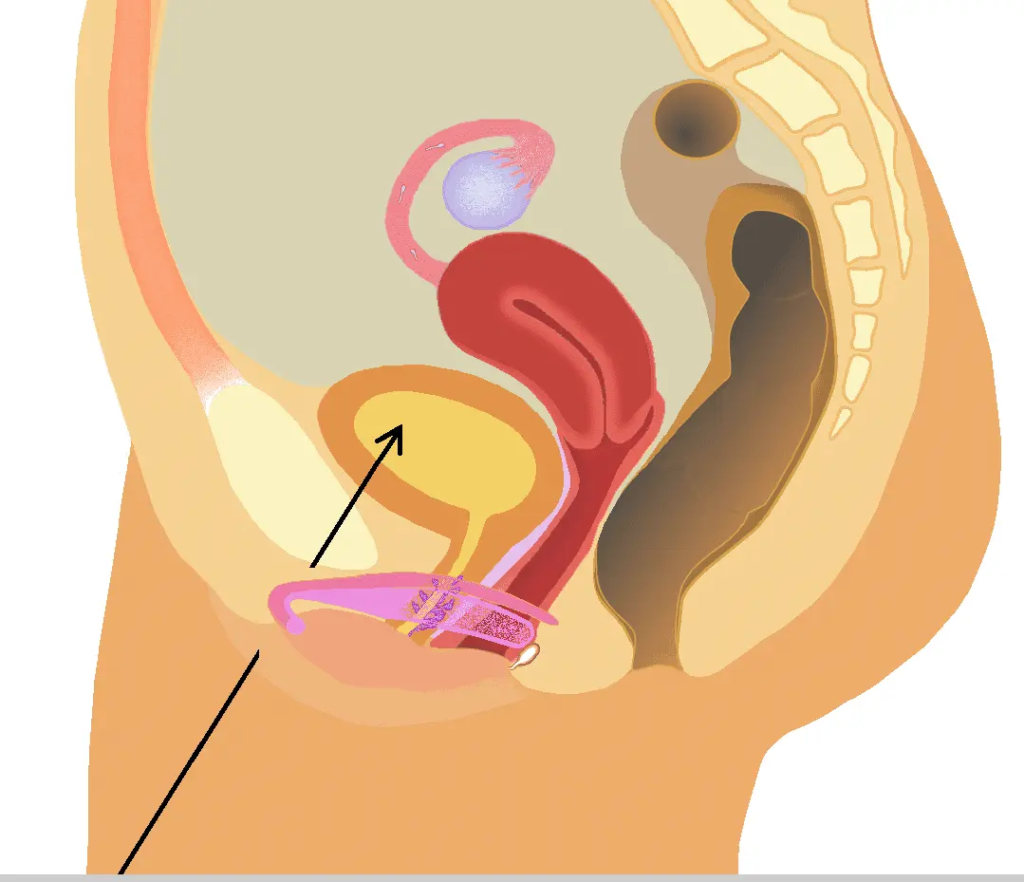

泌尿系統的解剖學差異

男生與女生的泌尿系統在結構上存在顯著差異,這直接影響排尿控制的能力。

男生尿道長約15-20厘米,從膀胱頸部延伸,經過前列腺、盆底肌群,最終至陰莖末端。尿道分為三段:前列腺尿道、海綿體尿道與膜尿道。其中,前列腺周圍有內括約肌(內尿道括約肌,為平滑肌,受自主神經控制)和外括約肌(外尿道括約肌,為骨骼肌,可任意控制)。這些括約肌確保尿液在適當時機排出。女生尿道則較短,僅約3-5厘米,從膀胱頸部直接延伸至陰道前壁開口。女生同樣擁有內外括約肌,但由於尿道短且靠近陰道與直腸,外部壓力(如懷孕或分娩)更容易影響控制。

根據解剖學描述,男生尿道較長確實提供額外阻力,但這並非「說停就停」的首要原因。關鍵在於外括約肌的強度與盆底肌群的協調。研究顯示,兩性皆可透過收縮盆底肌(Kegel運動)中斷尿流,但女生因解剖位置,較易受激素變化影響而導致肌力減弱。

女性的尿道開口在陰唇內,並非像男性一樣離身體有一段距離,而且尿道的方向向下。

女性為何較難中斷排尿?

雌激素會使平滑肌與骨骼肌的張力下降,這也解釋了為何女性在更年期後,因雌激素下降,反而可能出現尿失禁或頻尿的現象。

尿道長度與壓力傳導

男性尿道長,尿液在排出過程中需經過較長的通道,這為外括約肌提供了更多的控制點。女性尿道短,尿液一旦進入尿道,較難被「拉回」。